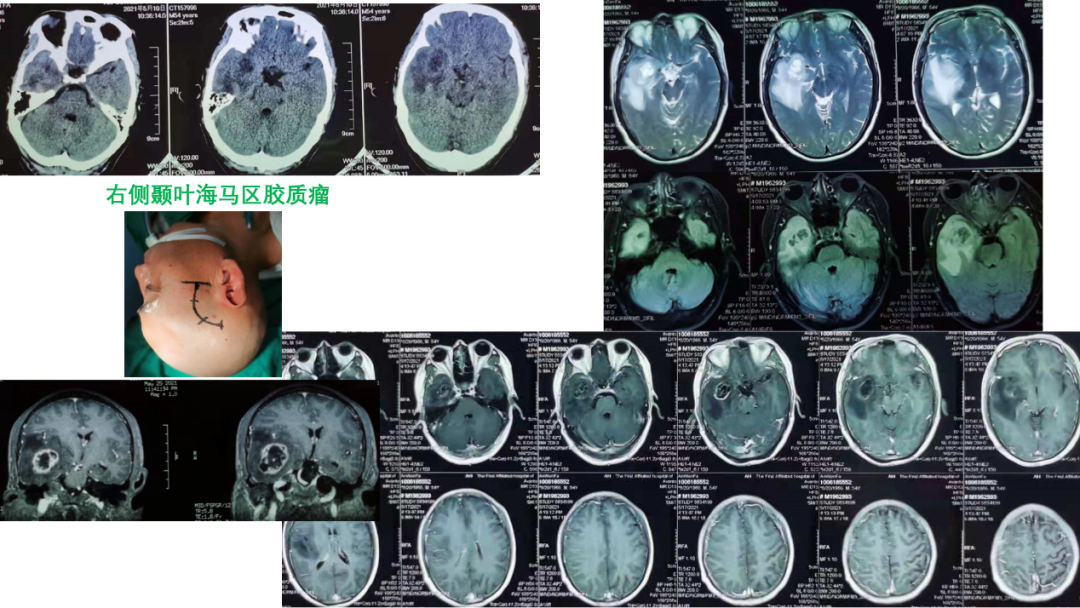

病例介绍

01

02

03

04